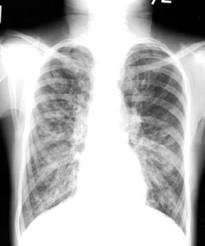

Del 24 al 30 de septiembre se está celebrando, de forma simultánea, en cinco hospitales de referencia en el tratamiento de esta enfermedad en España, la Semana de la Fibrosis Pulmonar Idiopática. Una conmemoración, que será a nivel mundial, de esta enfermedad huérfana que actualmente no tiene cura, y que tarda menos en causar la muerte que muchos tipos de cáncer.De hecho, la media de supervivencia es de dos a cinco años. Por ello, es imprescindible dar a conocer la enfermedad y poner el énfasis en la importancia de la investigación para ofrecer una esperanza a los afectados.